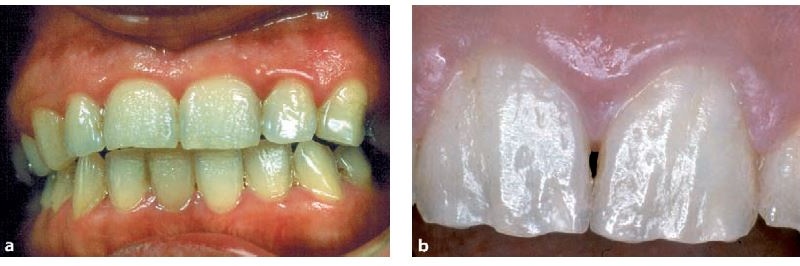

Tetratsükliini liigtarbimise tõttu värvunud hambad

Fluoroos

Fluoroosi

Emaili hüpoplaasiad

– Hammaste krooni kaltsifitseerumise häired, emaili hüpoplaasiad, on üsna sagedased. Need on nähtavad vahelduvate värvi- ja ehituse muutustena hamba pinnal.

– Hüpoplaasia on tingitud emaili tootvate rakkude normaalse talitluse häirumisest, mida tavaliselt

põhjustavad välised tegurid (näit. nakkused).

– Liigne fluor tekitab emaili defekte, kuid Soomes on see nähtus harv, sest põhjavees on fluorisisaldus harva kõrge. Fluori puudus hammaste ehituses ei ilmne, kuid email on kaariese tekkele vastuvõtlikum.